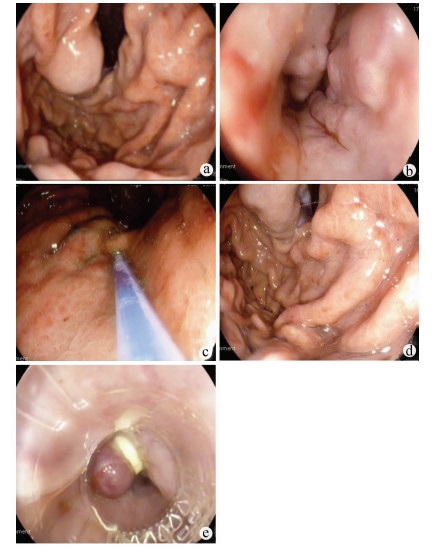

以亚急性肝衰竭为首发表现的IgG4相关性自身免疫性肝炎1例报告

2022, 38(1): 170-173. DOI: 10.3969/j.issn.1001-5256.2022.01.028

摘要(1571) HTML (431) PDF (3941KB)(81)

摘要: